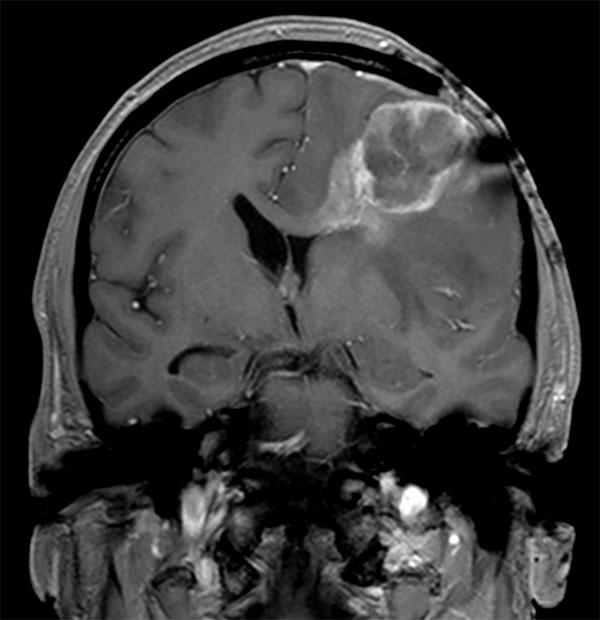

Coronal T1w FFE (post-gado)